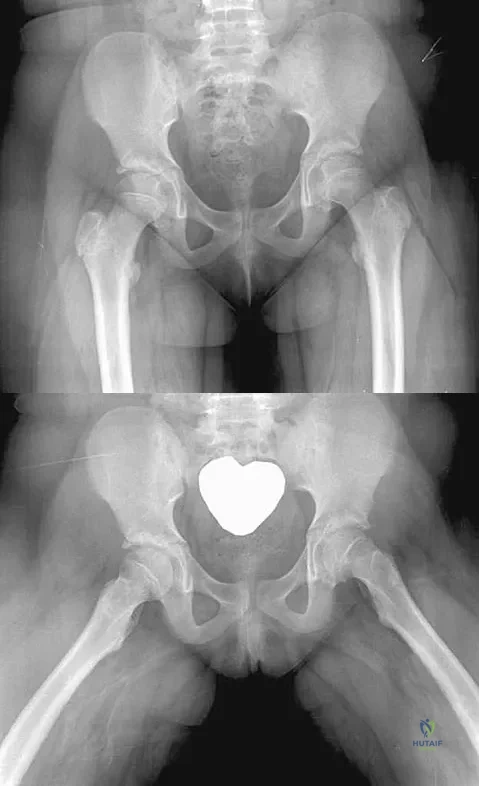

An obese 10-year-old boy has had left groin pain and a limp for the past 2 months. Examination reveals decreased abduction and internal rotation. Laboratory studies show normal renal function and an elevated thyroid-stimulating hormone (TSH) level. AP and frog lateral radiographs of the pelvis are shown in Figures 30a and 30b. What is the best course of action?

Explanation